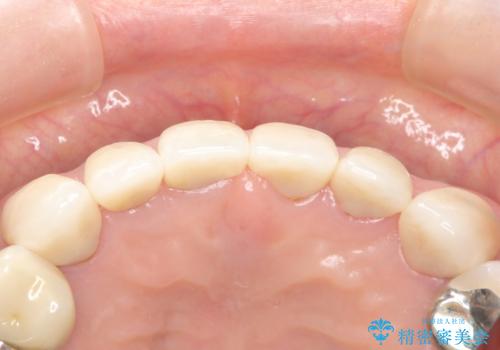

治療した上の前歯6本は全く問題なく、「獅子舞みたいだった前歯を綺麗にして下さってありがとうございました!」と再度お礼を言って下さいました。

4年半前のクラウン装着時と変わらず、まるで天然歯のように自然に見えました。

患者様の良好なセルフケアと精密な適合の良いクラウンにより、歯肉の腫脹や退縮も認められませんでした。